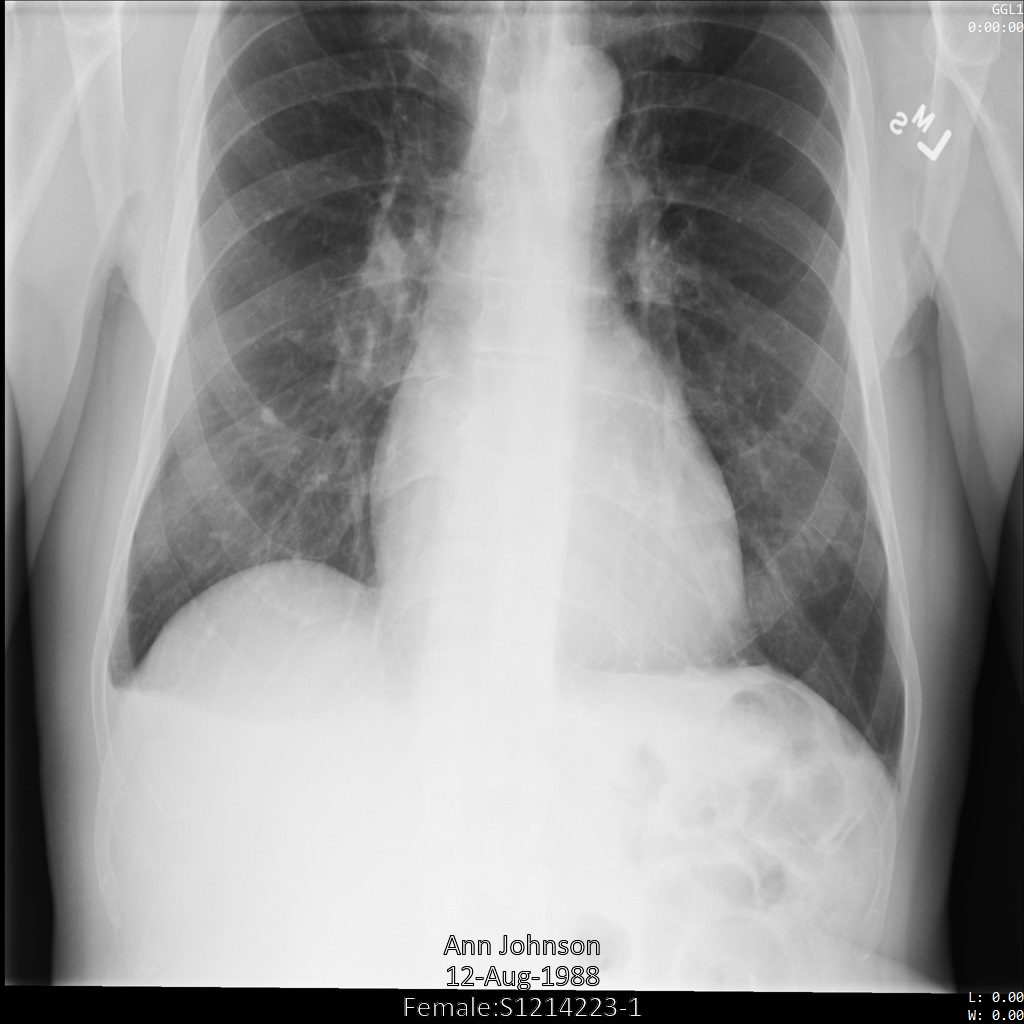

En la siguiente imagen, se muestra una radiografía sin ocultamiento de un paciente:

Después de enviar la imagen a la API de Cloud Healthcare mediante la opción REDACT_SENSITIVE_TEXT, la imagen aparece de la siguiente manera:

Puedes ver que ocurrió lo siguiente:

- Se ocultó el elemento

PERSON_NAMEen la esquina inferior izquierda de la imagen - Se ocultó el elemento

DATEen la esquina inferior izquierda de la imagen

El sexo del paciente no se ocultó porque no se considera texto sensible de acuerdo con los Infotipos de DICOM predeterminados.